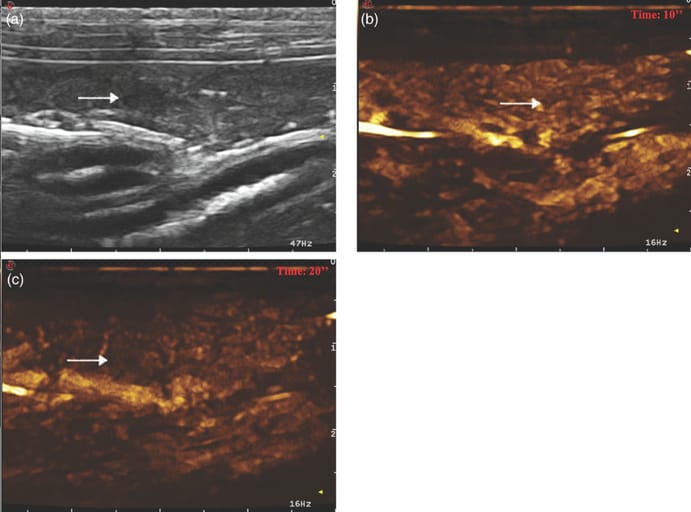

Example of a nodular hyperplasia showing hypoechogenicity with absence of acoustic enhancement at ultrasound (US); diffuse and homogeneous distribution of the contrast medium, with isoenhancement and a solid enhancement pattern during the wash-in phase at contrast-enhanced US; no wash-out. (a) Image obtained from US examination; (b) image obtained at time to enhancement; (c) image obtained at time to peak. Arrow indicates the lesion.